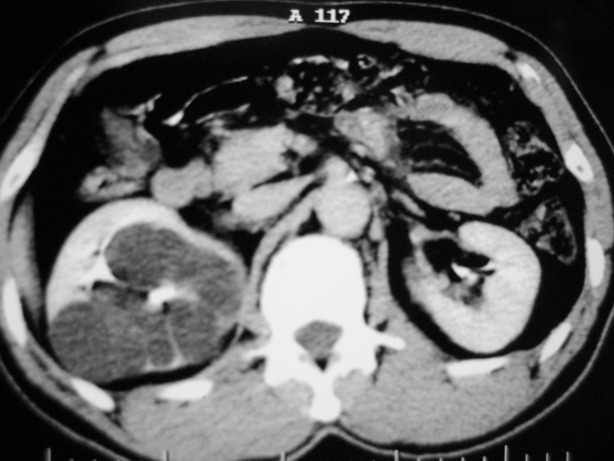

收集期:

肾盂旁多囊性占位,有实性成分,增强有轻度强化,收集期病变内无造影剂显影。诊断肾盂旁囊肿,有实性成分无法解释,查书后诊断为:多房性囊性肾瘤!!不知大家同意否?????????对本病知道不多,望大家不吝赐教!!

支持多发囊肿(所谓实质部分其实是肾实质)

右肾多发囊性低密度影,囊内有增强的隔及实性组织,考虑囊性肾癌。